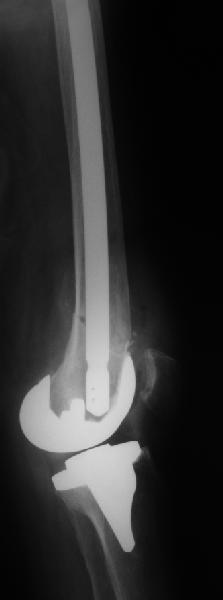

Отправитель: Alexander Chelnokov 20 Апрель 2011, 00:15

Больше 10 уже. Были 1 механическая неудача (сломалась очень тонкая ножка) и 1 глубокая инфекция.

Приходится индивидуально делать под конкретную ножку, с предпритием ЦИТО это получается за несколько дней и недорого.

Были пока только переломы и несращения. С деформациями как-то не попадались пока.

Нам каждый случай интересен, так что давай созвонимся-спишемся, возможно, получится что-то совместно сделать.